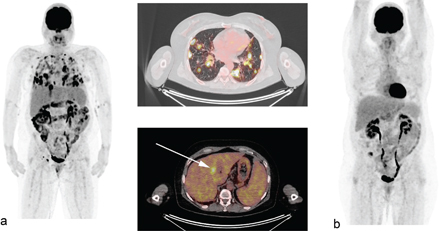

Fig 4

Figure 4. 57-year-old woman with history of 2 HL relapses, the last one treated by Nivolumab. One year after starting nivolumab (PD1 immune check point inhibitor), she developed enlarged mediastinal and abdominal lymph nodes, diffuse pulmonary lesions (SUVmax=27.4) and a hepatic lesion, all with intense FDG uptake A, Biopsies revealed aseptic granuloma including well-formed giant cells consistent with sarcoid-like reaction. PET/CT after corticosteroids (b) showed improvement with a complete metabolic response of all lesions.